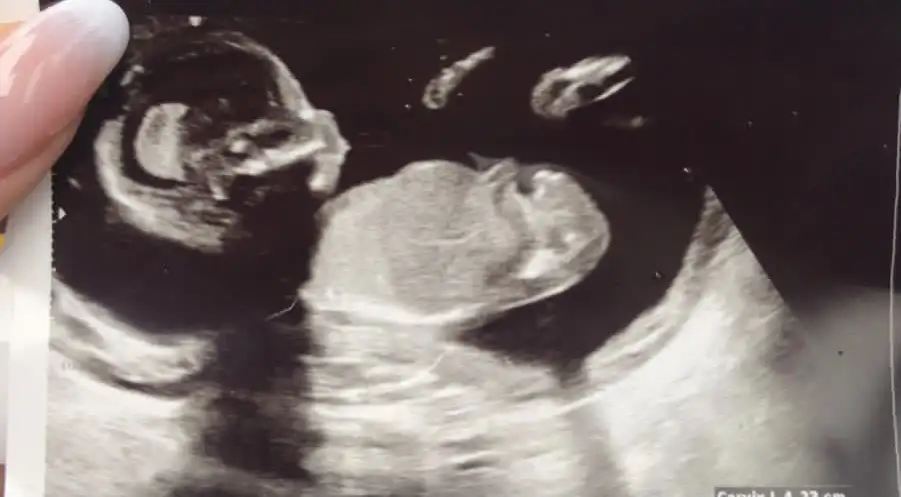

Kız görünüyor12+3üz, bize de bakar mısınız rica etsek?

Kız gibi sankiMerhaba ablamin bebegi bu yorumlarmisiniz benimkini bilmistiniz simdi sira bundaIkra meyra

Eki Görüntüle 2805103 Eki Görüntüle 2805104